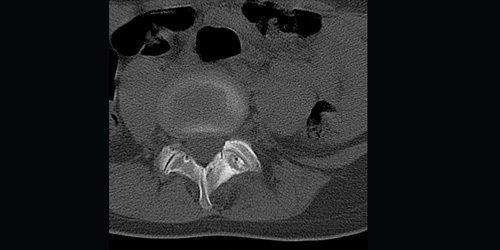

Chondrosarcoma is a malignant tumor of the bone that originates from cartilage tissue. Chondrosarcoma usually occurs after the age of 40 and is more common in men.